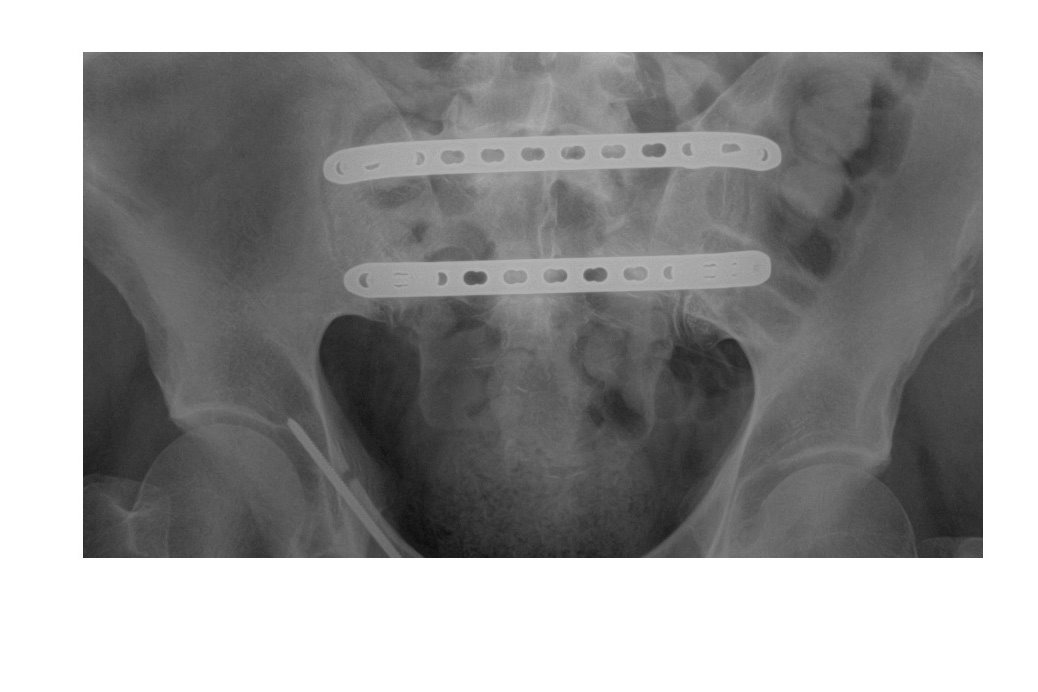

In one of the several surgeries I had, metal plates with various screws were installed in my sacrum, in order to support it and allow it to rebuild, since it suffered several serious fractures.

With great joy I can share that I am very grateful to find out that the metal plates have worked and that the sacrum has completely consolidated. However, the plates are causing me great difficulties when I walk, sit, or sleep. One screw has loosened, and the other screws are causing excruciated pain to the point that not even strong medications can help me to alleviate the pain. During the past few months, the discomfort and the limitations these meal plates produce have been increasing.

I have been consulting with several specialists about removing the metal plates, concerned that if they stay in place they may cause more damage and the possibility of greater disability.

The orthopedic surgeon has explained to me that removing the plates and screws will greatly improve the discomfort, so I need to undergo a new surgery as soon as possible.

In one of the several surgeries I had, metal plates with various screws were installed in my sacrum, in order to support it and allow it to rebuild, since it suffered several serious fractures.

With great joy I can share that I am very grateful to find out that the metal plates have worked and that the sacrum has completely consolidated. However, the plates are causing me great difficulties when I walk, sit, or sleep. One screw has loosened, and the other screws are causing excruciated pain to the point that not even strong medications can help me to alleviate the pain. During the past few months, the discomfort and the limitations these meal plates produce have been increasing.

I have been consulting with several specialists about removing the metal plates, concerned that if they stay in place they may cause more damage and the possibility of greater disability.

The orthopedic surgeon has explained to me that removing the plates and screws will greatly improve the discomfort, so I need to undergo a new surgery as soon as possible.